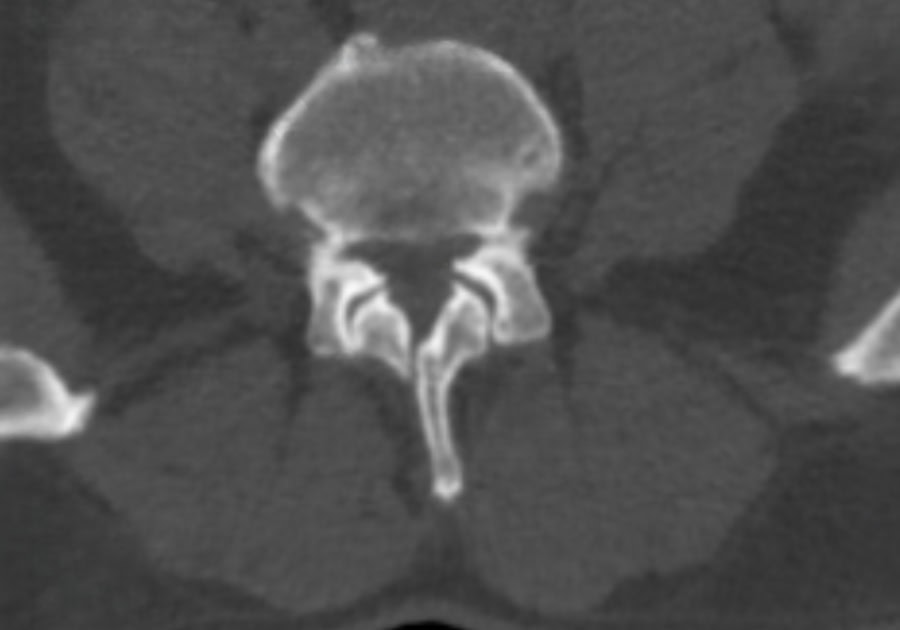

Preop.